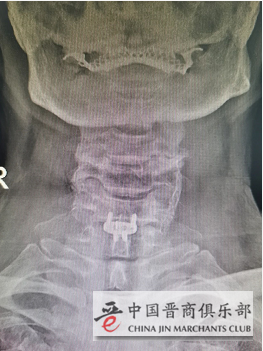

患者术后影像

韦向荣主任介绍,长期以来,以前做颈椎间盘突出症的手术使用的是钛板为主要术式,但部分患者由于钛板放在椎体前方可出现咽部不适、吞咽困难等并发症。颈椎前路零切迹椎间融合器的使用,具有对颈椎及椎前结构干扰和破坏小、手术创伤小、出血少等优点,有效降低了术后患者吞咽困难及邻近节段退变的发生,从而降低术后并发症,提高临床疗效。